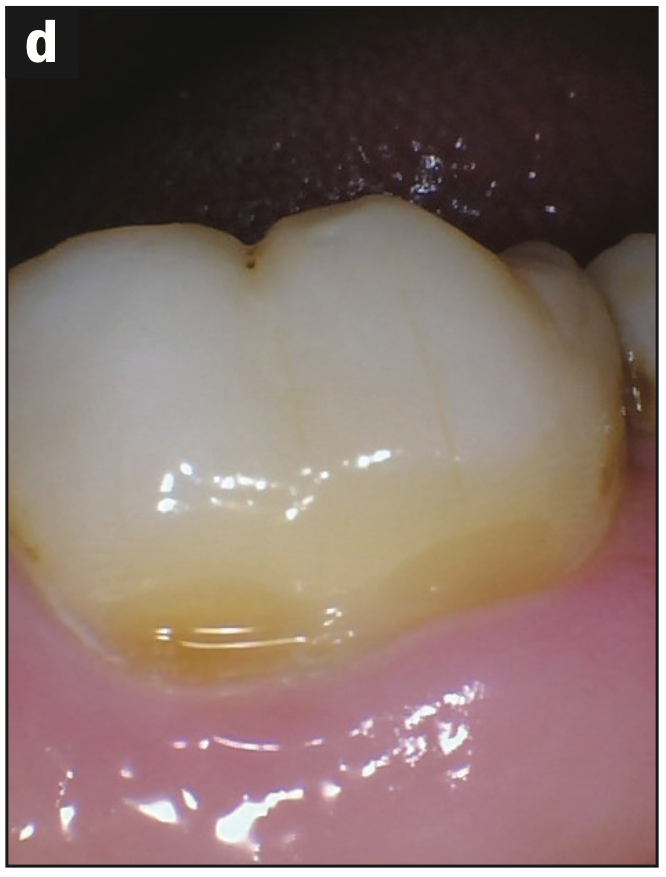

- Abfraction with decay (Figures 2a and 2b)

- Abfraction lesions (Figures 2c and 2d)